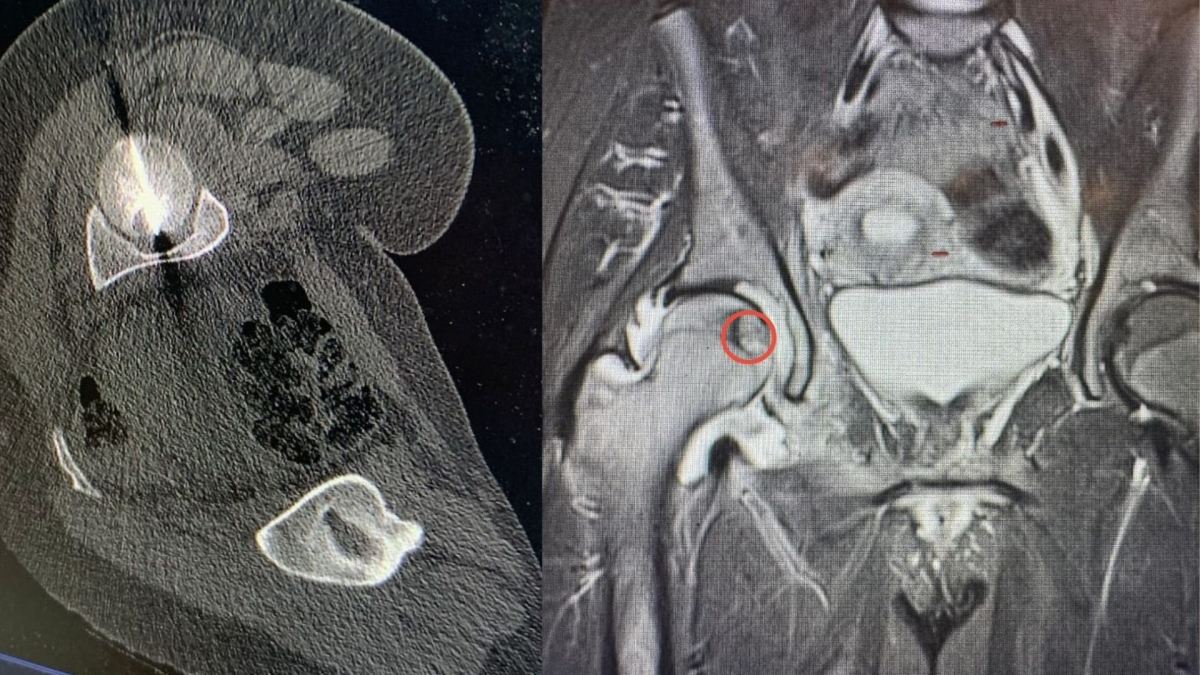

نيروز الإخبارية : أجرى مستشفى الجامعة الأردنية، تدخلا علاجيا متقدما في قسم الأشعة، استطاع من خلاله فريق طبي متعدد الاختصاصات معالجة ورم عظمي في موقع شديد الحساسية داخل رأس عظم الفخذ لمريض ثلاثيني.

ويعد هذا الموقع من أكثر المواضع صعوبة في الوصول إليها جراحيا، ما يجعل الخيارات التقليدية محدودة ويزيد من تعقيد التعامل مع الحالة، لاسيما وأن المريض كان يعاني من آلام حادة أثرت بشكل كبير على قدرته على الحركة وممارسة أنشطته اليومية.

وبين البطوش، أن الفريق الطبي نجح في الوصول إلى مركز الورم بدقة عالية باستخدام تقنية التصوير الطبقي المحوري (CT Scan)، تلا ذلك إجراء الكي بالتقنية الحرارية باستخدام المايكروويف، وهي من أحدث التقنيات العالمية في علاج أورام العظام دون الحاجة إلى التدخل الجراحي المفتوح.